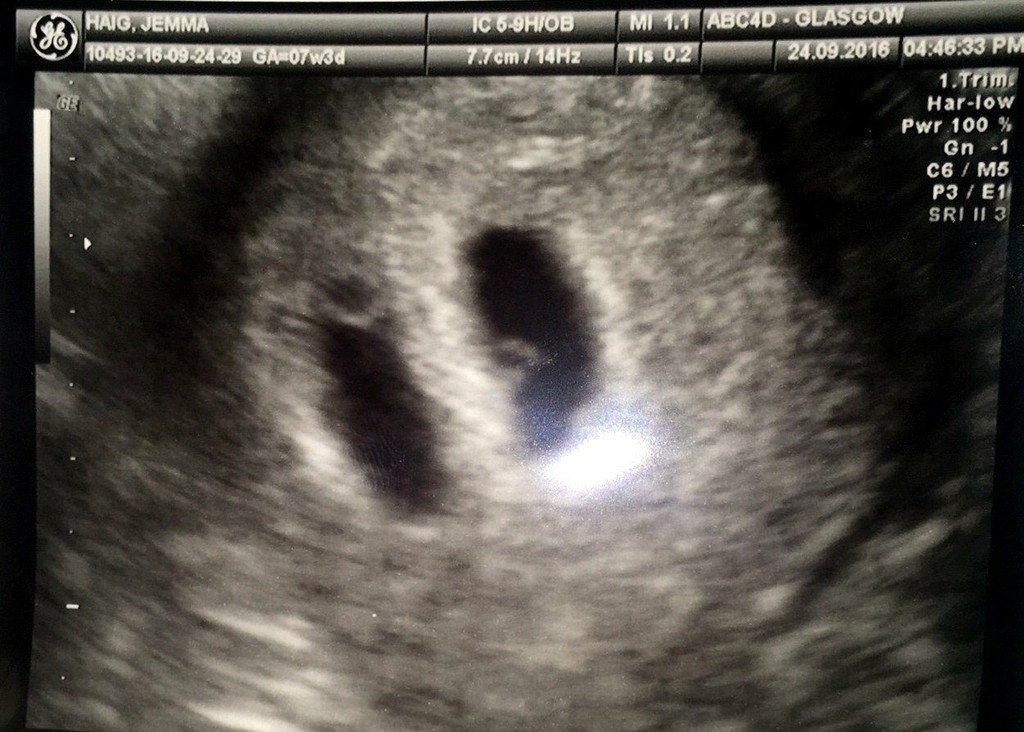

Manželský pár Jemma Haig so snúbencom Murray McKirdym boli v radostnom očakávaní, no jeden triviálny ultrazvuk v priebehu chvíle rozdupal ich sny na prach.

Lekári zistili, že Jemma nečaká jedno, ale rovno tri deti. Na tom by nebolo nič zlé, naopak, no výsledky prehliadky ukázali, že všetky deti neprežijú. Scan ukázal, že Jemma v bruchu nosí dva plody, oddelené plodovou blanou.

Jedným bol syn Thomas a v druhom vaku sa nachádzali siamské dvojčatá, ktoré mali spoločný respiračný, tráviaci a obehový systém. Boli spojené hrudníkmi a mali jedno srdce.